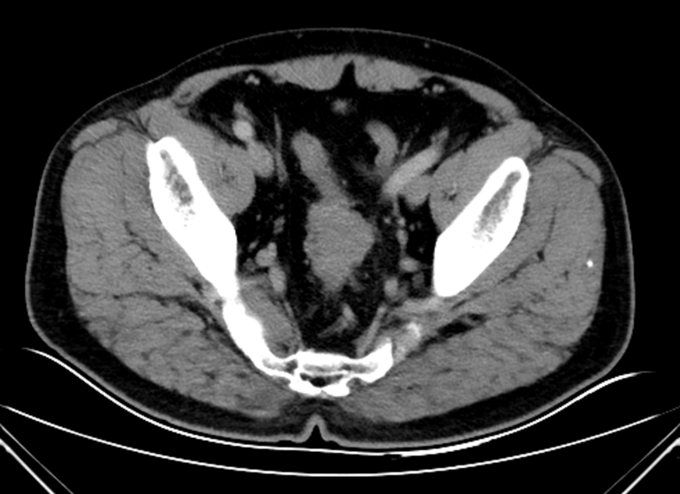

查体:腹平坦,未见胃肠型及蠕动波,未见腹壁静脉曲张。全腹软,未触及腹部肿块,压痛(-),反跳痛(-),肌紧张(-)。肝脾肋下未触及,Murphy’s 征(-),肝区叩击痛(-),移动性浊音(-)。肾区叩击痛(-)。肠鸣音正常,4次/分。肘膝位,肛门进指顺利,进指约7cm,未触及明确肿物,退指指套无染血。 辅助检查:马应龙肛肠医院肠镜检查显示:距离肛门60cm30cm见两枚大小约0.3*0.2cm息肉,表面光滑,广基、无蒂、无色泽略红,距肛门15cm处可见一半环行菜花样粘膜隆起。表面凹凸不平,出血、糜烂与污秽交织在一起,隆起向腔内生长,至管腔狭窄,镜身未通过,取病理5块。 术前腹部CT:乙状结肠下段肠壁增厚